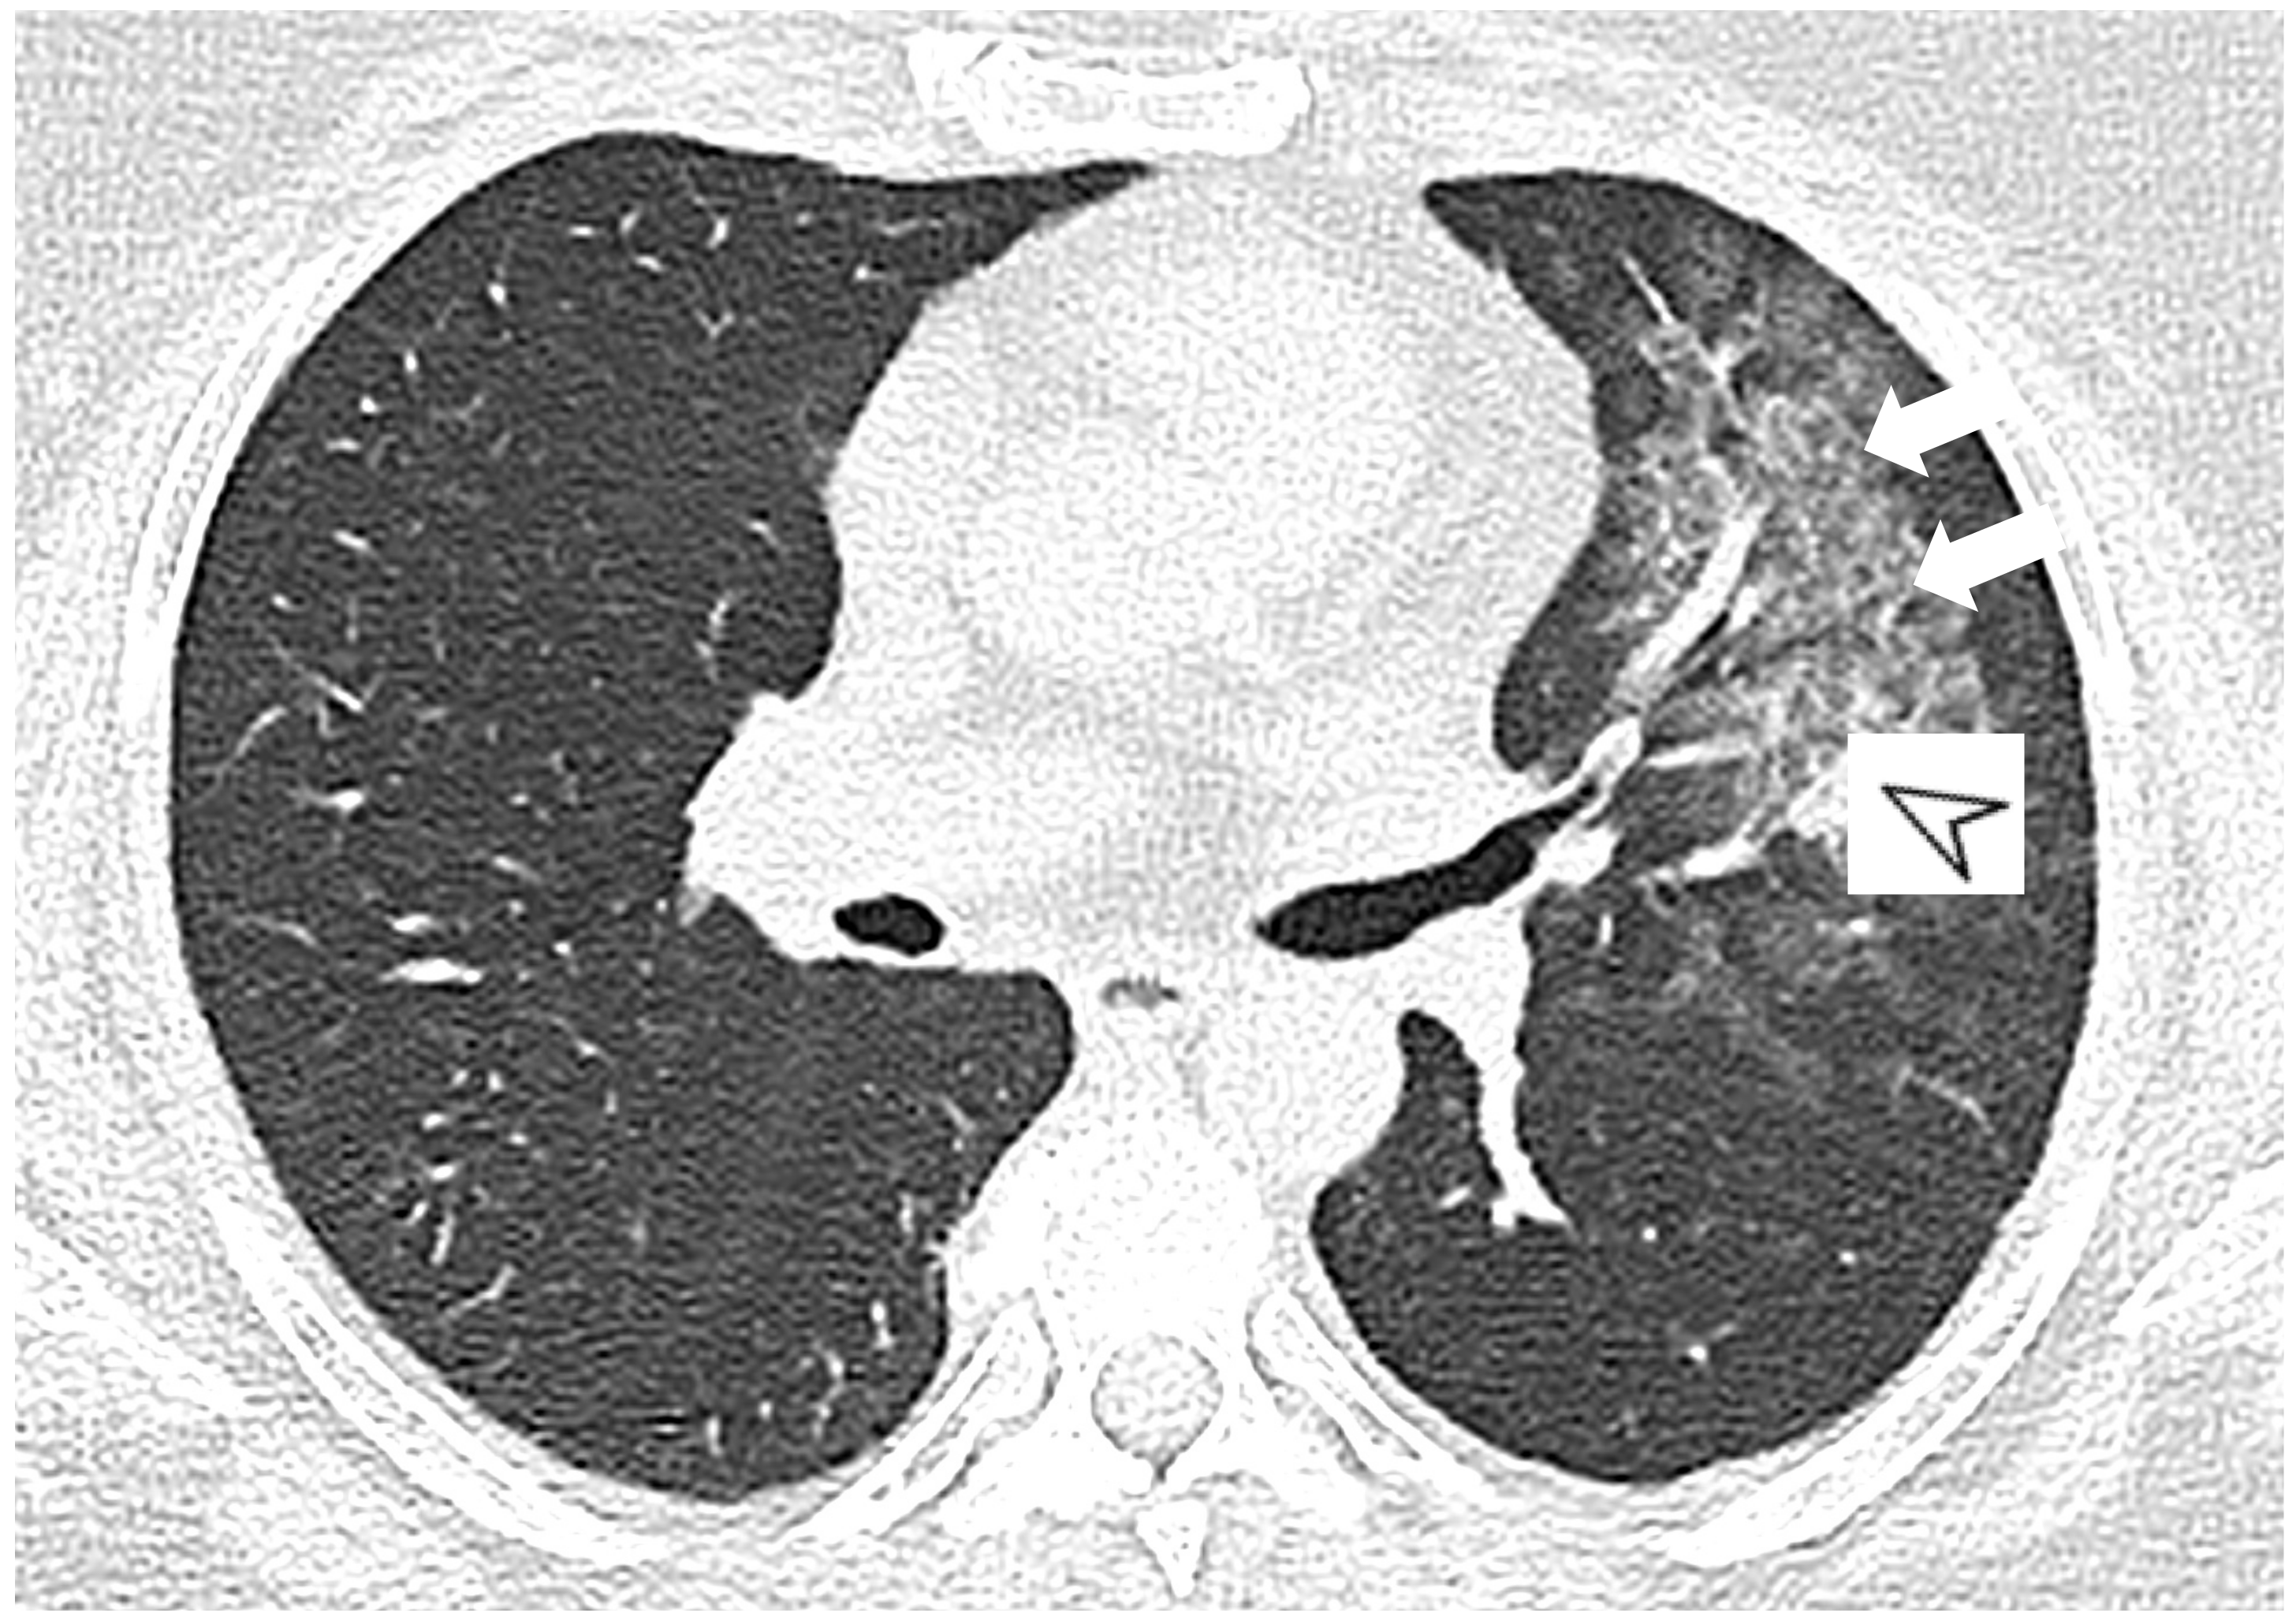

2.3. Microscopic Polyangiitis (MPA)

| MPA | GGOs due to hemorrhagic alveolitis (common); consolidation, nodules with centrilobular distribution (less common) |